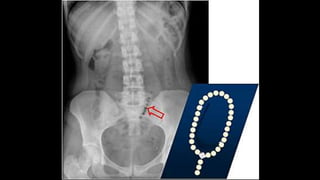

SIGNO DEL COLLAR DE PERLAS

• Hilera de burbujas en disposición vertical u oblicua, en

decúbito supino o en bipedestación.

• Representa pequeñas cantidades de aire atrapado en las

válvulas conniventes del intestino delgado,

predominantemente lleno de líquido.

• Se presenta en la obstrucción mecánica del intestino

delgado, aunque rara vez también puede verse en el íleo

paralítico, gastroenteritis o tras la aplicación de un enema

salino.

SIGNO DEL COLLARDE PERLAS • Hilera de burbujas en disposición vertical u oblicua, en decúbito supino o en bipedestación. • Representa pequeñas cantidades de aire atrapado en las válvulas conniventes del intestino delgado, predominantemente lleno de líquido. • Se presenta en la obstrucción mecánica del intestino delgado, aunque rara vez también puede verse en el íleo paralítico, gastroenteritis o tras la aplicación de un enema salino.